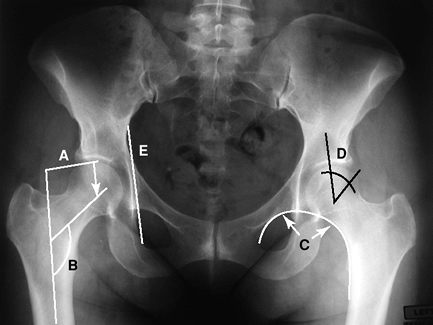

central line of the femoral neck and shaft. Normal 125 degrees with a

range of 120 to 140 degrees.

inferior border of the superior pubic ramus and the medial border of

the femoral neck. Helpful in evaluating the relationship of the femoral

head to the acetabulum. A break in the Shenton line indicates migration

of the femoral head.

center of the femoral head to the edge of the acetabulum. A second line

is drawn vertically to the center of the femoral head to form the

incident angle.

ischium to the medial border of ilium. Penetration medial to this line

indicates protrusion.

![]() |

|

Figure 2-10 Radiographic landmarks of the femur. A, femoral offset; B, femoral neck shaft angle; C, Shenton line; D, center edge angle of Wiberg; E, Köhler line.